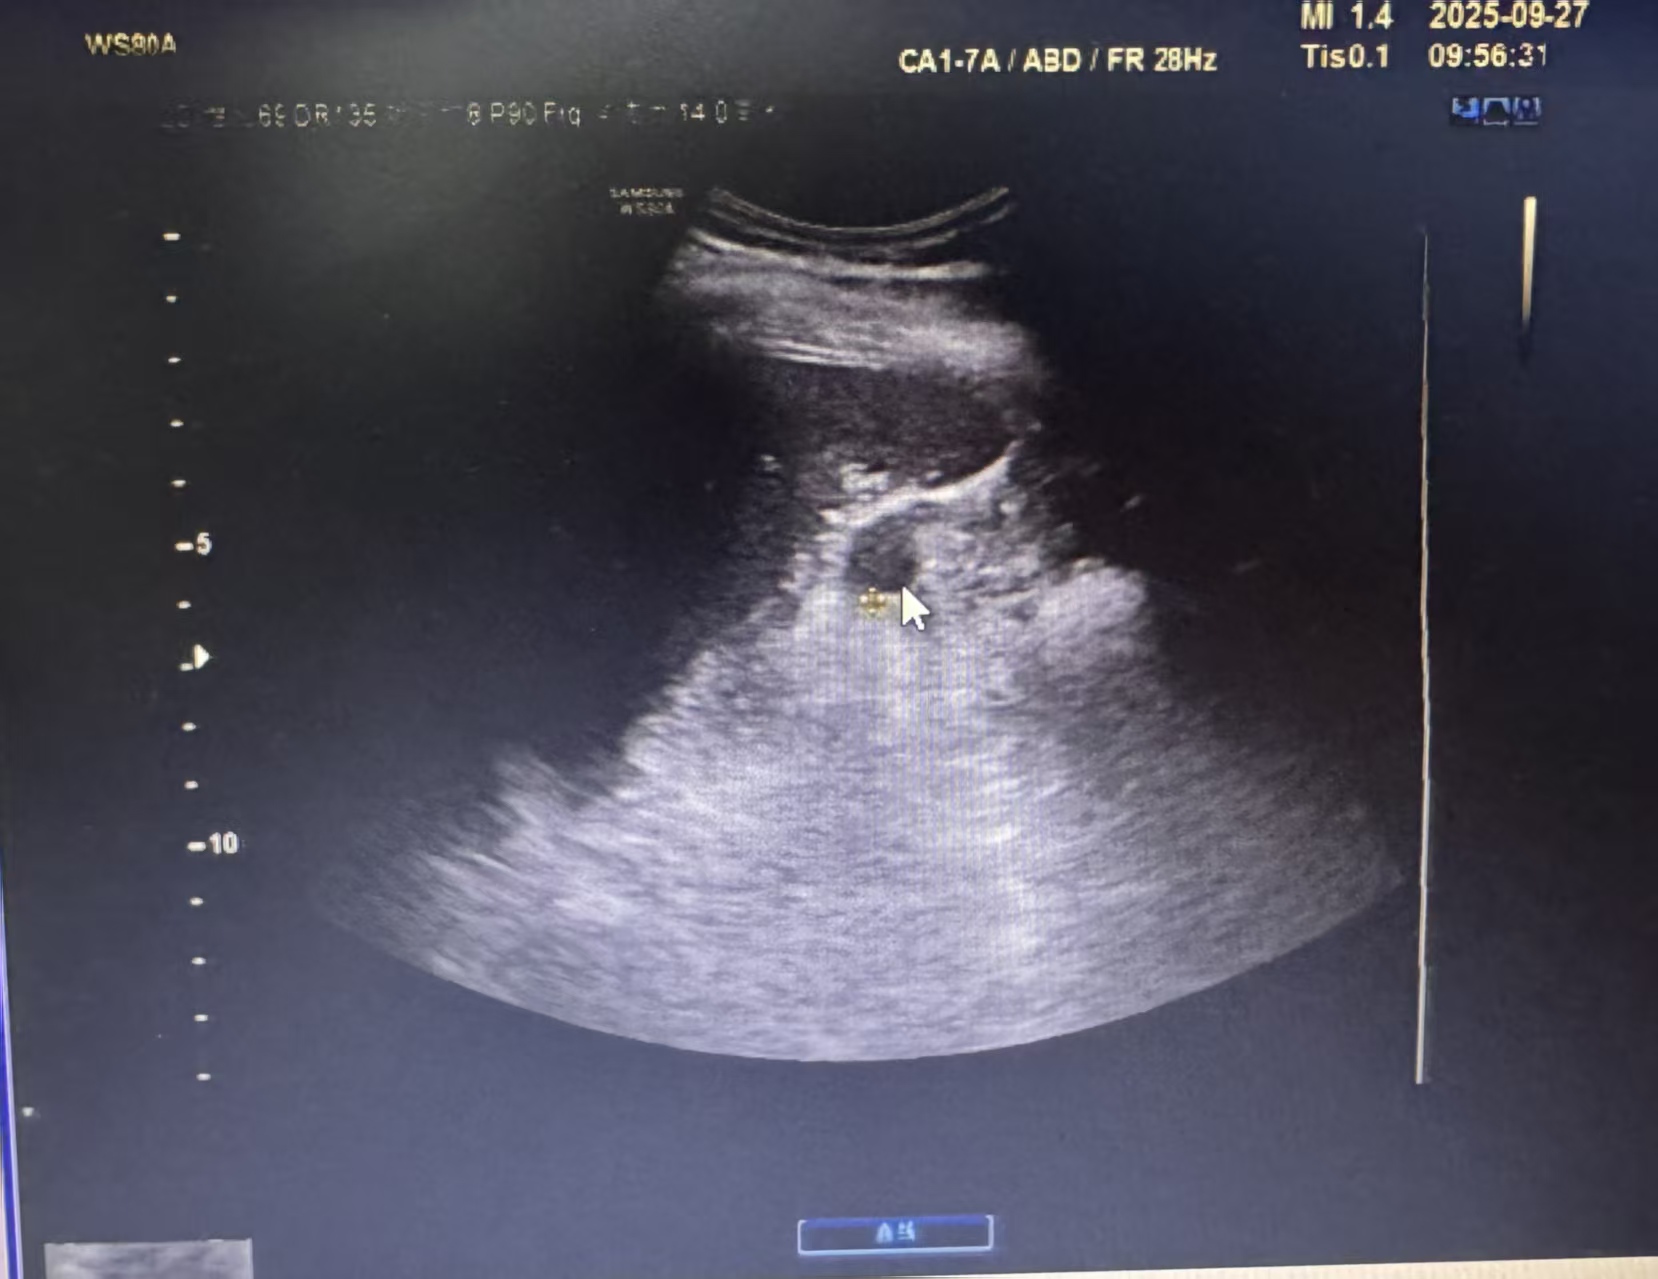

超声眼里的“小间谍”长啥样?

做超声检查时,副脾逃不过医生的“火眼金睛”。它通常有几个明显特征:

1. 位置固定

最爱躲在脾脏的“家门口”,也就是脾门附近,像个忠诚的小跟班。偶尔也会跑到胰尾附近。

2. 外形圆润

大多呈边界清晰的圆形或椭圆形,直径通常在1-2厘米,像个光滑的小球。

3. 善于伪装

这点最关键!在超声图像上,副脾的回声质地和主脾脏一模一样。这就是判断它是副脾而非其他肿物的核心依据。